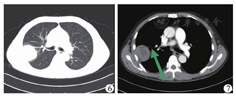

例4 受者术后恢复良好,顺利出院。于术后3个月因胸痛入院,肺部CT检查提示右肺上叶出现团块状实变影(图6、图7),已侵犯肺血管,入院第3天行经皮肺穿刺活检,活检病理提示右下肺真菌感染(毛霉菌感染倾向),加用两性霉素B脂质体(逐日递增至维持剂量1 mg·kg-1·d-1)抗感染治疗;入院第4天受者出现胸闷、胸痛加重伴有咯血,床旁胸部X线片检查提示右侧胸腔积液,予以胸腔闭式引流术,引出红色血性胸水约150 ml;第5天晚胸闷、胸痛症状进一步加重,并出现血压、心率、血氧下降,血胸最终导致受者死亡。受者病情进展快、病情凶险,考虑系毛霉菌容易侵犯血管所致血胸最终导致受者死亡。

肾移植受者发生侵袭性真菌感染的易感时间分为三个阶段:术后1个月内、术后1~6个月及半年后[7,8]。本组4例受者肺部毛霉菌感染发生时间有3例在术后3个月内,1例在术后第7个月,确诊主要是通过支气管镜检、肺泡灌洗液培养、经皮肺穿刺活检等方法,鉴于其临床表现的不典型性,诊断又大都依赖有创的组织病理学检查,移植医师对此应有一定的认知及警觉性。由于毛霉菌嗜血管性生长,极易侵犯肺脏大血管,在行经皮肺穿刺活检时需格外小心,术前需认真阅片,加强术前风险评估。例4从肺部CT检查中可以清晰看出病灶已侵犯肺脏动脉,穿刺后需重点注意有无胸闷、胸痛、血胸等表现,一旦毛霉菌侵犯大血管致其破裂,可引起胸腔大出血导致受者死亡。